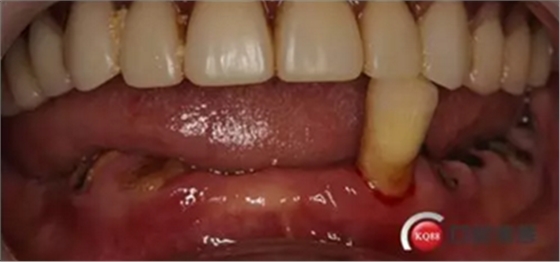

檢查:上頜無牙頜假牙穩(wěn)定性尚可,下頜3435364243殘根;33殘冠1-2度松動,其他牙齒缺失;CBCT檢查:下頜牙槽骨前牙區(qū)骨高度足,后牙區(qū)骨高度最低為8mm,骨寬度足。

1)術前檢查,拍攝臨床照片及CBCT檢查,制取活動義齒參考模型,指導后期最終修復的牙齒排列

2)術前準備及手術過程,測量血壓及血糖,簽種植知情同意書;嚴格遵循無菌操作,局麻下采用微創(chuàng)技術于323436分別植入osstem4.0X10,4.0X10,4.5X7; 434446分別植入osstem4.0X1O,4.0X10,4.5X7.初期穩(wěn)定性均達到了35N.CM以上;嚴密縫合,止血,種植體位點和方向與設計一致。